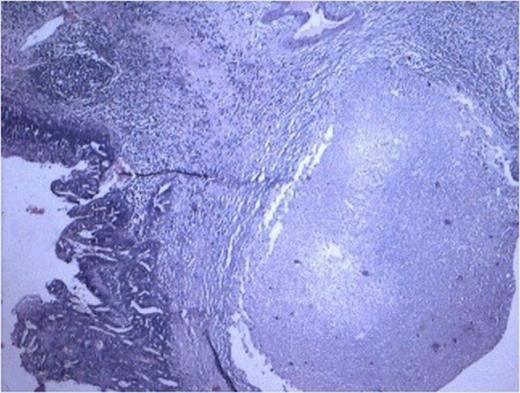

Gross examination of the specimen showed a multi-cystic sac-like structure measuring 11 x 6 x 2.5 cm along with the attached ureter. There was no visible renal tissue macroscopically. Cut surface of specimen showed multiple loculi with varied appearance and thinned out wall at some places with intervening thickened areas at others (Fig 1).